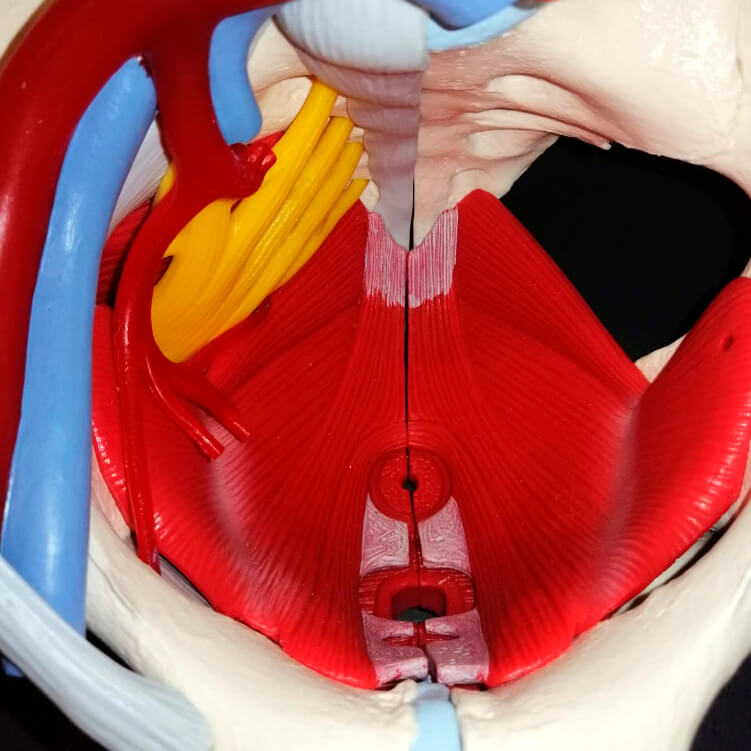

Deberías hacerte una valoración de suelo pélvico si: - Sientes a veces un fuerte deseo de orinar (urgencia) - No estás segura de saber localizar los músculos del suelo pélvico - Toses o estornudas con frecuencia (enfermedades respiratorias, alergias) Llama para cita al 965332837

Deberías hacerte una valoración de suelo pélvico si:

- Sientes a veces un fuerte deseo de orinar (urgencia)

- No estás segura de saber localizar los músculos del suelo pélvico

- Toses o estornudas con frecuencia (enfermedades respiratorias, alergias)

Llama para cita al 965332837